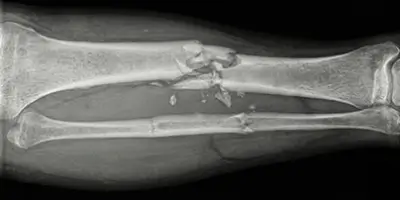

Parçalı kırık (komminüte kırık), kemiğin birden fazla parçaya ayrıldığı ciddi kırık türüdür. Nedenleri, belirtileri, teşhisi ve tedavisi hakkında bilgi.

Patolojik kırık, kemiğin altta yatan hastalık nedeniyle zayıflaması sonucu hafif darbelerle oluşan kırık türüdür. Nedenleri, belirtileri, teşhisi ve tedavisi hakkında bilgi.